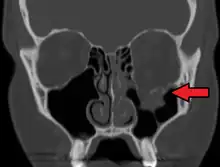

| Blowout fracture | |

|---|---|

| Other names | Orbital floor fracture |

| An orbital blowout fracture of the floor of the left orbit. | |